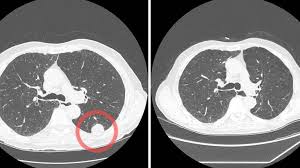

Entropy Free Full Text Classification Of Covid 19 Coronavirus Pneumonia And Healthy Lungs In Ct Scans Using Q Deformed Entropy And Deep Learning Features Html

Entropy Free Full Text Classification Of Covid 19 Coronavirus Pneumonia And Healthy Lungs In Ct Scans Using Q Deformed Entropy And Deep Learning Features Html from www.mdpi.com